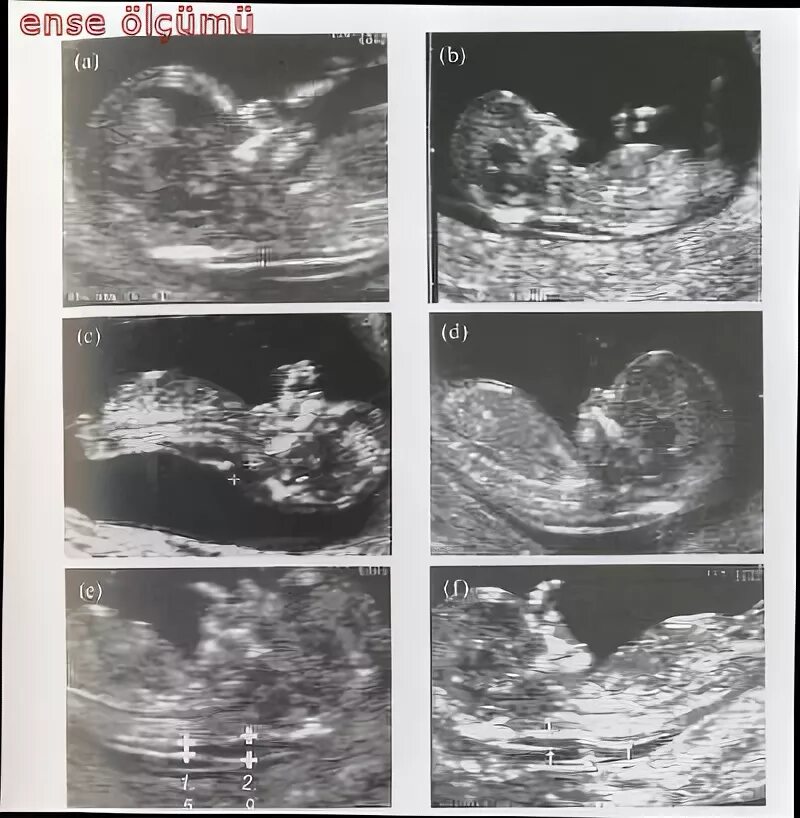

Воротниковое пространство 5